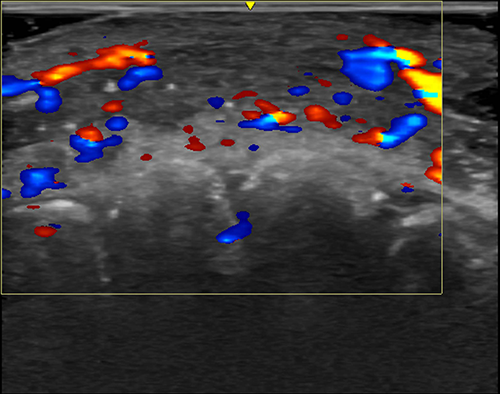

Ultrasound can aid in treating complications from cosmetic filler injections, according to research being presented this week at the RSNA annual meeting.

A serious complication from hyaluronic acid fillers is vascular occlusion—the disruption of blood flow in arteries—resulting from misplacement of filler material.

The most common finding—in 42% of cases—was absent flow to perforator vessels, which connect superficial to deep arteries in the face. In 35% of cases, flow was absent in major blood vessels, and this finding was significantly associated with lateral nasal artery involvement.

“If injectors are not guided by ultrasound, they treat based on where the clinical findings are and inject blindly,” Dr. Sigrist said. “But if we can see the ultrasound finding, we can target the exact place where the occlusion occurs. Rather than flooding the area with hyaluronidase, we can do guided injections that use less hyaluronidase and provide better treatment results.”

Ultrasound criteria are well established for mapping out blood flow in areas such as the carotid vessels and the vessels of the limbs. But in the delicate, complex and highly variable vasculature of the face, radiologists need a reference standard to map out common patterns of filler-related complications. Dr. Sigrist’s team provides a framework that can help radiologists recognize these patterns, make timely decisions and treat with precision before serious damage occurs.